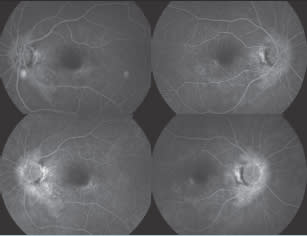

| A 70-year-old woman is evaluated for decreased vision in her left eye. She has Sjögren syndrome, posterior vitreous detachment and epiretinal membrane in both eyes and a history of pigmentary changes observed in the left eye for 6 years. She has hypertension, hypothyroidism and rheumatoid arthritis. She is taking enalapril (Vasotec), levothyroxine (Synthroid), and hydroxychloroquine (Plaquenil) (200-300 mg for 20 years). Note the mild ERM present and eventually the loss of the OS/IS junction with pigment atrophy. Owing to these changes, it was recommended the patient discontinue the Plaquenil.

Figure 4. Fluorescein angiogram, March 2010

Figure 5. Fluorescein angiogram, January 2011

On visits in July 2009, March 2010 and January 2011 (top to bottom), the patient's visual acuity OS was 20/20, 20/25−1 and 20/25+2.

On visits in July 2009, March 2010 and January 2011 (top to bottom), the patient's visual acuity OD decreased from 20/20 to 20/20−2 to 20/25−2. |